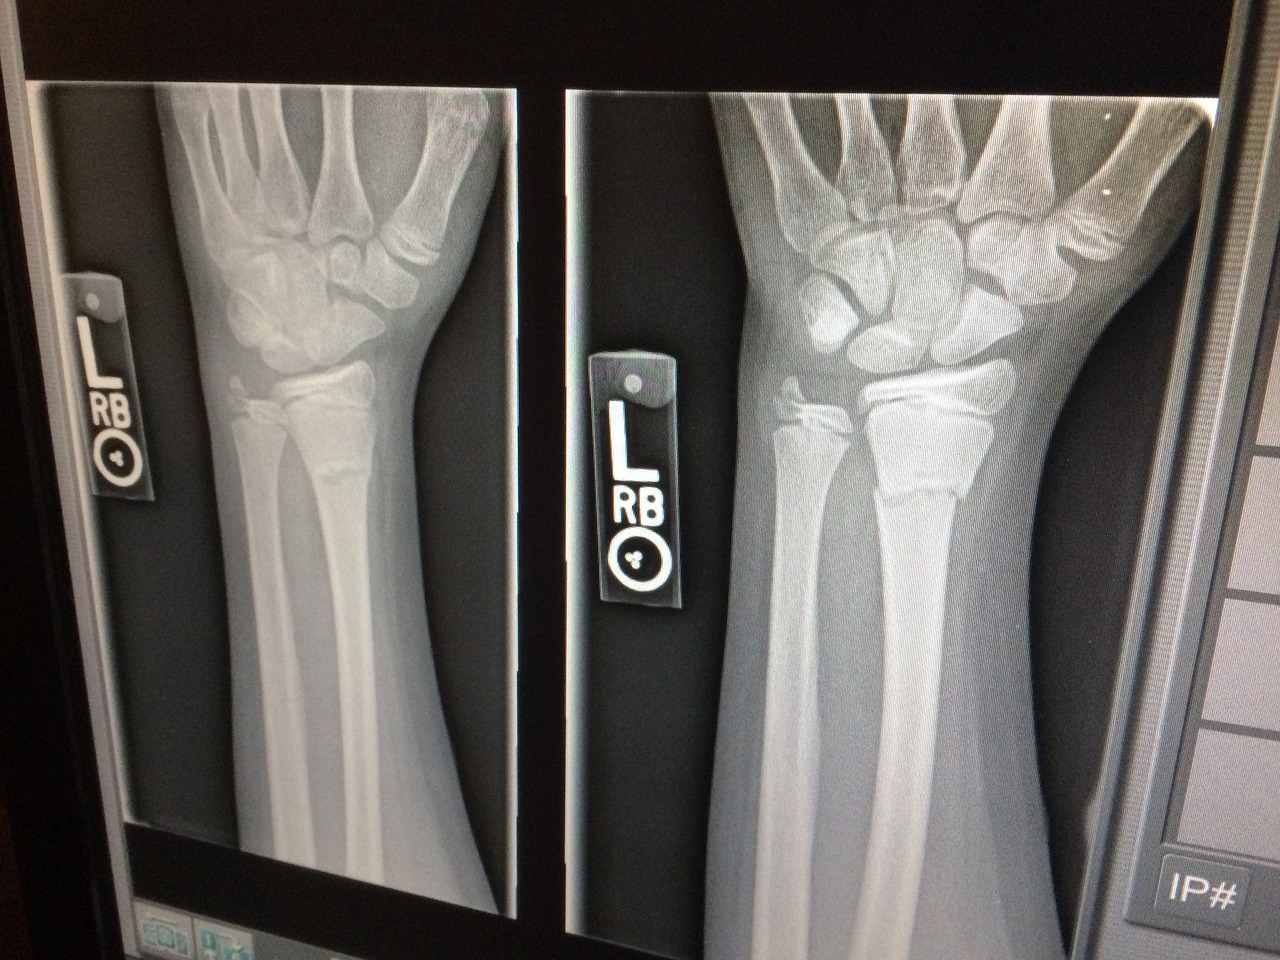

A cast is just as effective as surgery for treating older patients with bone fractures near the wrist, according to international researchers. The team looked at 276 patients aged 70-89 who suffered a broken wrist that didn’t penetrate the skin – with 213 receiving a cast and 63 having plates or pins placed during different types of surgery.  Within the first year, 19 patients experienced complications, with the most common being complex regional pain syndrome (in five patients who underwent surgery and two who received casts) and carpal tunnel syndrome (in six patients who received casts). After one year, the team found no difference between the groups in terms of disability of the arm, shoulder, and hand, or regarding range of motion. While more research is needed, the research could help avoid unnecessary surgery in older patients.

A recent study in the Journal of Orthopaedic Research found that cast immobilization is as effective as surgery for treating older patients with bone fractures near the wrist.

The study included 276 patients aged 70–89 years who suffered a distal radius fracture that didn’t penetrate the skin and that was treated conservatively or surgically between August 2018 and January 2022. Cast immobilization was used on 213 patients, whereas the other 63 had plates or pins placed during different types of surgery.

Nineteen patients experienced complications within the first year, with the most common being complex regional pain syndrome (5 patients who underwent surgery and 2 who received casts) and carpal tunnel syndrome (6 patients who received casts).

After 1 year, no statistically significant differences were found between the groups in terms of disability of the arm, shoulder, and hand, or regarding range of motion.